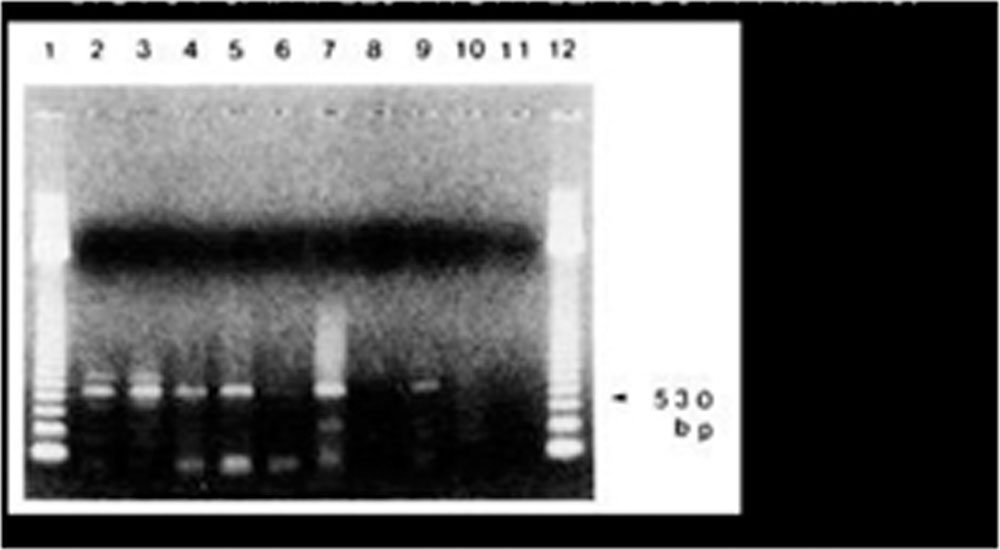

38% showed acute anterior uveitis and 62% showed chronic anterior uveitis. It was granulomatous in 83% with the predominant clinical feature being iris sphincter atrophy and dilated pupil with large mutton keratic precipitatesand anterior chamber cells and flare. 17 % of patients presented with a non- granulomatous iridocyclitis although that is not a usual presentation in uveitis. Cataract was noted in 33% of patients. On morphological evaluation, posterior subcapsular cataract was the most common feature and both senile and complicated cataract were seen. Several of our patients had dilated pupil due to iris sphincter atrophy. Vitritis was present in 3% of patients and was seen as grade 2 cells with vitreous haze. Fundus examination was normal in all patients. 12% of patients had scleritis of the nodular type. Those with scleritis showed resolution with topical steroids with no recurrence and a scraping was not performed on them. Treatment for iridocyclitis was 1% atropine eye drops,1% prednisolone acetate eye drops and oral steroids in the dose of 1mg per kg bodyweight In those with no resolution to this treatment for more than 3 weeks, an anterior chamber paracentesis was performed. RT- PCR performed on the aqueous humour of 12 patients with recalcitrant uveitis showed detection of DNA of M. leprae in 3 of them. A smear in these patients showed the presence of live and dead bacilli. Microscopy showed the typical morphology of fully formed live bacillus and beaded dead bacilli both existing in the same sample. After completion of treatment, the onset of uveitis in the paucibacillary type occurred within 1 year in 9% of patients, 2 years in 33% and within 3 years in 11%. Those with multibacillary leprosy had recurrence of uveitis after 3 years of completion of treatment. No patients had uveitis before that time period.

Conclusion: Acute anterior uveitis in leprosy is more common in the tuberculoid type despite completion of treatment. RT- PCR on aqueous is useful in chronic uveitis and requires ocular follow up even if histopathology is negative for the bacillus.Evaluation and analysis of aqueous humour by PCR has shown that DNA assays can be very sensitive in identifying bacilli and their DNA. Patients who have completed treatment are more likely to have persisting M. leprae bacilli in the aqueous humour in the paucibacillary type. Also the recurrence of uveitis is earlier in these patients than the multibacillary type. We found in our study that the commonest cause of defective vision is chronic uveitis with complicated cataract which is treatable if detected early. It may be required to start anti leprosy treatment again when live bacilli are seen in the aqueous humour even if the systemic status has settled. PCR can certainly ascertain the diagnosis by detecting even few bacilli from a small sample. This may actually be helpful in breaking the chain of leprosy transmission. PCR of aqueous humour can be adopted as a routine in all patients who present with anterior uveitis after completion of leprosy treatment. The prevalence of uveitis and blindnessin leprosy can vary between different populations. A programme for screening of leprosy should continue throughout the course of treatment and at regular intervals even after completion of treatment for both multibacillary and paucibacillary forms.

- Figure 4: PCR detection of M. leprae DNA from aqueous humor samples

Figure 4: RT- PCR detection of M. leprae DNA from aqueous humor samples